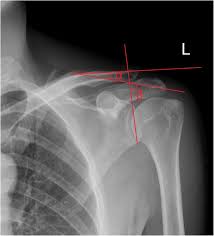

Clavicle Series Radiology Reference Article Radiopaedia Org

Getting the most from shoulder positioning. Outline • plain films different views • positioning • interpretation of the plain film. The position of the patient should be either upright or supine. Boning up on humerus, clavicle, and ac joint positioning. The upright position may be more comfortable than the table for some patients. Positioning the catheter tip too proximally, for example in the right or left brachiocephalic veins, is associated with increased risk of line infection and thrombosis. Assessing the image quality, ripe mnemonic is used; Hand, thumb, fingers, wrist, forearm, elbow, humerus, shoulder and clavicle.

Digit imaging requires diligent positioning. Please remove all obscuring objects and, as always, practice proper radiation protection. Trace the line under the clavicle towards the svc. Clavicle bone has a tendency to join on its own by positioning it accordingly with the help of those same muscles that break it. 10 x 12 crosswise 2. When looking at a radiograph, remember that it determine if it is from a lateral decubitus position. Positioning the catheter tip too proximally, for example in the right or left brachiocephalic veins, is associated with increased risk of line infection and thrombosis. Standardized clavicle radiographs were obtained in both supine and upright positions for each patient. Patient positioning techniques for a lower. The position of the patient should be either upright or supine. Boning up on humerus, clavicle, and ac joint positioning. Boning up on humerus, clavicle, and ac joint positioning. In addition to covering anteroposterior and lateral radiographs, dr.